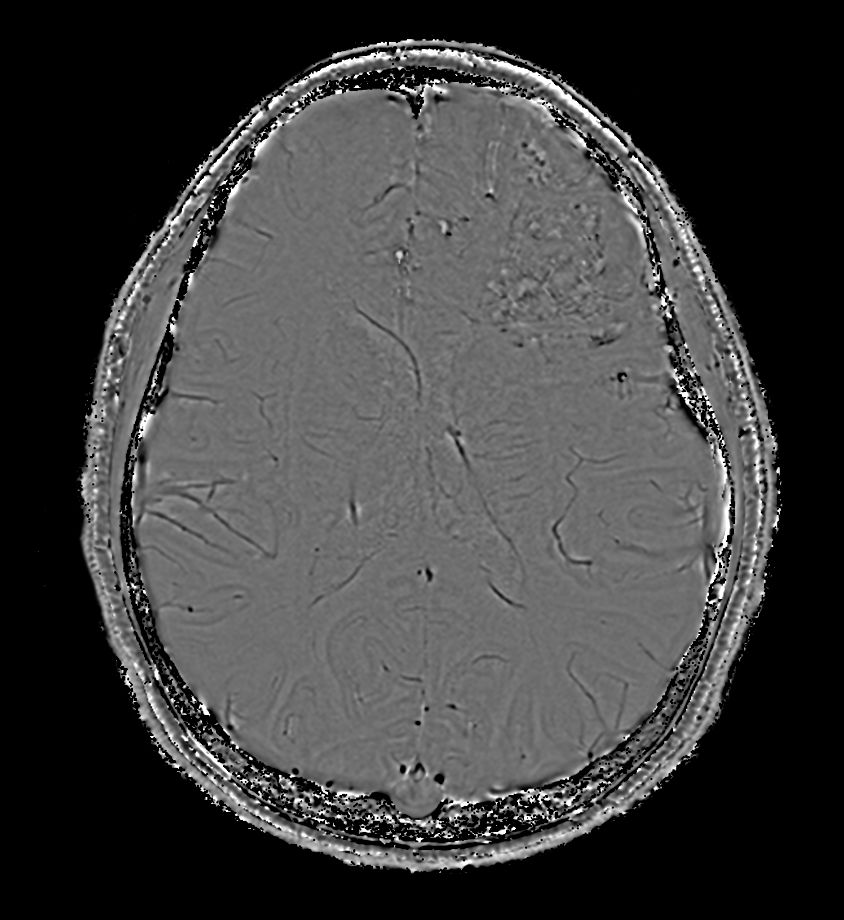

3D T1w TFE +gado - Axial reformatCompressed SENSE

3D T1w TFE - Axial reformatCompressed SENSE